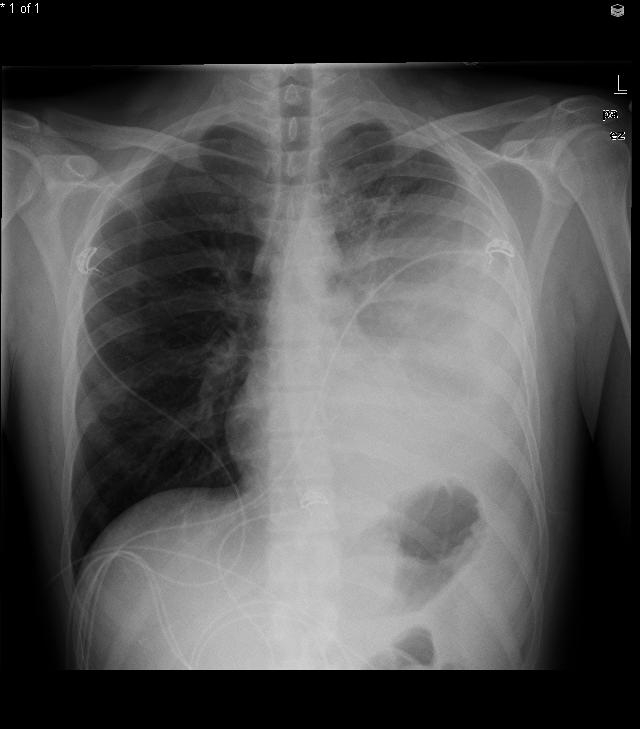

The most likely diagnosis in this patient is constrictive pericarditis, a condition marked by pericardial fibrosis and obliteration of the pericardial space. Constrictive pericarditis impairs ventricular filling during diastole, causing patients to experience symptoms related to decreased cardiac output (fatigue and dyspnea on exertion) and signs of venous overload (elevated JVP, ascites, and pedal edema). Kussmaul's sign, defined as lack of the typical inspiratory decline in central venous pressure, and the presence of a pericardial knock (early heart sound after S2) may also be seen. Sharp x and y descents are characteristically seen on central venous tracing. Pericardial calcifications can sometimes be seen on chest x-ray and, when present, help confirm the diagnosis.